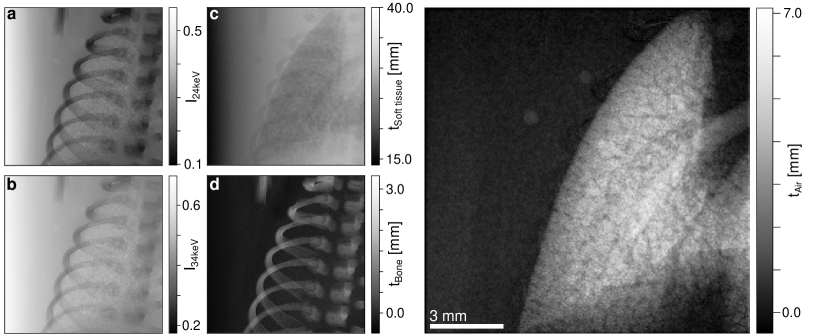

Finally, we take a look at the scientific problem stated at the outset of this paper: spectral PBI of the lung. Results of a deceased neonatal rabbit kitten are presented in Fig 5. As we needed to take spectral images sequentially, the animal was fixed in agarose gel to prevent deformation during the measurement. Radiographic images of the chest area containing one side of the lung were again taken at , shown in (a), and , shown in (b). The chest consists primarily of two materials (besides air): soft tissue and bone, which are superimposed in the images. Naturally, not all soft tissues are the same, and the object also includes a large amount of agarose gel and the plastic sample container. However, the X-ray optical properties of these materials are approximately equal to those of soft tissue, and were considered as equal. For phase retrieval, we therefore used the theoretical values for cortical bone and soft tissue as defined by the International Commission on Radiological Protection (ICRP) [57]. Given that bone and soft tissue have very comparable X-ray optical properties to Al and PMMA, and our experiments were performed at the same X-ray energies, the observation that phase retrieval enhances the image of the weakly attenuating constituent can be translated to this system. After applying phase retrieval and material decomposition, we obtained thickness maps for soft tissue, , and bone, , which are presented in Fig 5 (c) and (d), respectively. The bone thickness image illustrates excellent material decomposition - all of the relevant bone structures, which includes parts of the ribcage, spine, and one limb, are well isolated from the soft tissues. Nonetheless, bone structures can clearly be identified in the soft tissue image. This is not caused by a residual bone signal but rather the lack thereof. By computationally separating soft tissue and bone, removal of bone leaves behind voids in soft tissue, which can be seen here. As we are primarily interested in the lung, we can virtually fill these voids by calculating the sum . Within our approximations, this represents the aggregate thickness of all materials that are not air, i.e. everything except for the lung air volume. The projected thickness of a cylindrical container follows a function of the form . We fitted this function in a region outside the lung and obtained a smoothly varying map of the background. Any deviations from this are consequently caused by the lung, and we subtracted from the fitted background to arrive at the positive projected air thickness within the lung, , depicted in panel (e). This gives us an isolated image of the projected lung air volume, free of bones, as was the goal of this paper. The trachea and fine-scale fluctuations in thickness due to the branch-like structure of the lungs are clearly visible. The two small, circular structures next to the lung are air bubbles formed in the agarose gel during sample preparation and, consequently, remain in the air-only image.